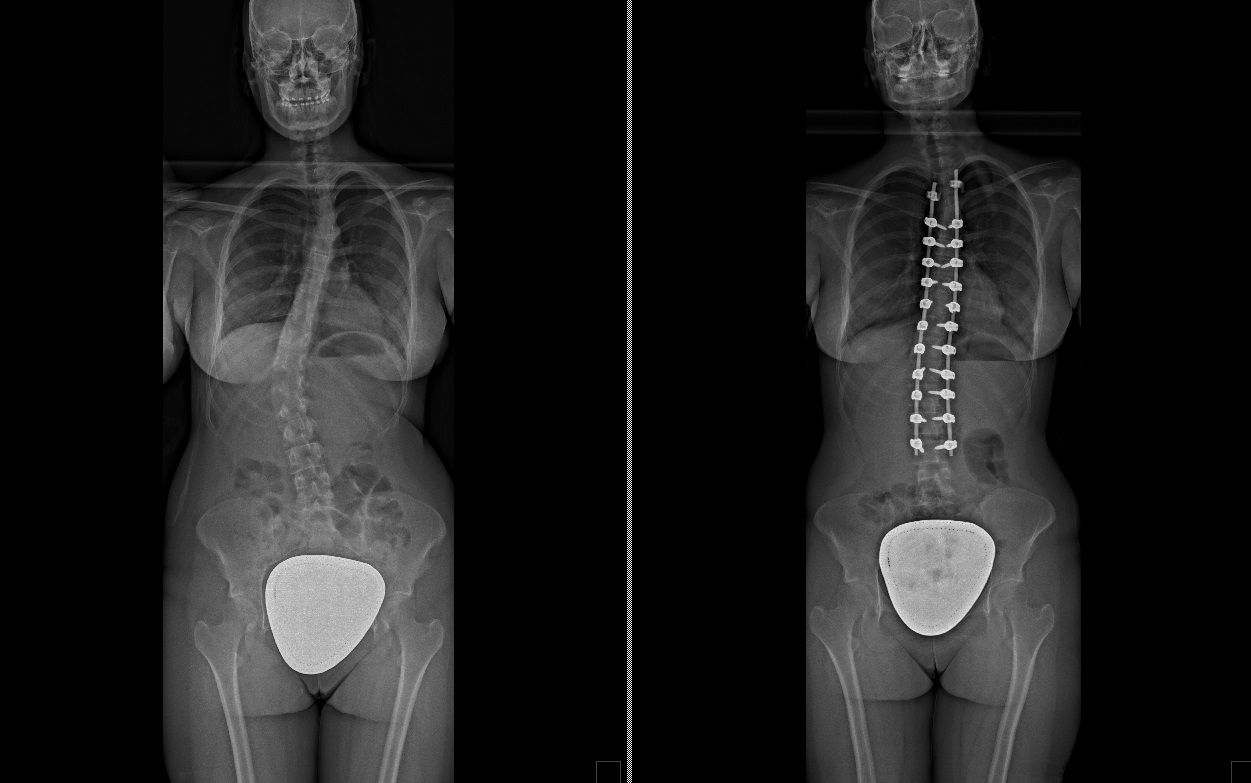

Laureato in Medicina e Chirurgia presso l'Università degli Studi di Napoli Federico II nel 2011, Specializzato in Ortopedia e Traumatologia presso la stessa Università nel 2017. Da subito ho dedicato i miei studi all'ambito della chirurgia vertebrale e della neurochirurgia. Infatti ho frequentato per 9 mesi tra il 2015 ed il 2016 i reparti di Neurochirurgia dell'IRCCS Neuromed di Pozzilli (IS) per apprendere le tecniche di trattamento delle Patologie della Colonna Vertebrale. Da allora il mio principale interesse è rivolto al trattamento conservativo e, dove necessario, chirurgico delle deformità della colonna vertebrale, sia dell’età dell’accrescimento che degenerative dell’adulto: scoliosi, dorso curvo, spondilolisi, spondilolistesi. Ulteriori campi di interesse sono il trattamento di lombalgia e lombosciatalgia, ernia del disco, stenosi del canale vertebrale, fratture vertebrali traumatiche o da osteoporosi (vertebroplastica), terapia del dolore osteoarticolare mediante tecniche mininvasive (radiofrequenze). Dal 2017 sono Consulente presso IRCCS Neuromed di Pozzilli (IS) con incarico di Responsabile del Centro per la Diagnosi e Cura delle Deformità Vertebrali e Scoliosi, dove svolgo la mia attività chirurgica in regime di convenzione. Svolgo la mia attività chirurgica in regime di solvenza e di convenzione assicurati presso la Clinica Ruesch di Napoli. Continuo costantemente la mia formazione con esperienze di perfezionamento nazionali ed internazionali. Infine, dal 2020 sono Docente per l'Università degli Studi di Roma "La Sapienza".

• Chirurgia vertebrale

Foto e video